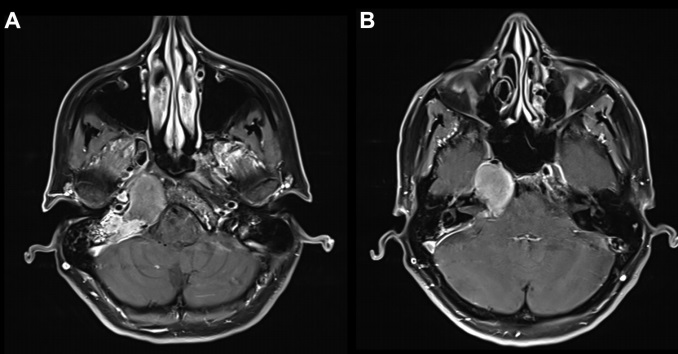

术前(红色箭头):A、B图显示位于右海绵窦中心的脊索瘤病变。病变集中在右侧海绵窦和翼骨上,并在右侧邻卵圆孔。

手术过程:神经内镜单鼻孔经蝶窦手术切除

术后(蓝色箭头):C图表示矢状位显示无肿瘤残余。D、E、F图显示轴位、冠状位脊索瘤被绝大部分切除。